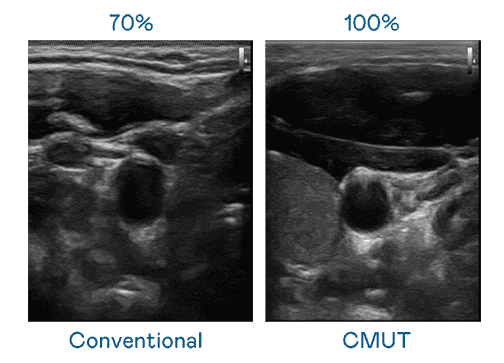

CMUT 技术是一种用电容式微机电元件来产生超音波讯号的技术。。。与传统 PZT 压电式技术相比,,,,CMUT 频宽增加 30%,,更宽频的超音波讯号让影像解析度大幅提升,,是实现高影像品质医疗超音波扫描、、、、促进精准医疗发展的关键技术。。

大频宽带来超清晰影像

超音波影像的解析度高低,,,首先取决于探头能发出的讯号频宽。。。2468BET CMUT 可提供高清晰的超音波讯号,,,提供高频宽、、高灵敏度、、影像纹理细节更高的超音波影像,,,,协助医护人员缩短影像判读时间及利用精准的医疗影像进行诊断。。。。